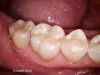

After a clean and neat cavity preparation, liner was placed on the deep cavity surface to mask the dark amalgam stain. The liner was light-cured for 20 seconds. A wide bevel was placed on the occlusal surface, and then a ring and matrix were placed. A selective enamel etching was performed with 37% phosphoric acid (Figure 3), rinsed, and dried. Universal bond was prepared by adding one drop from each bottle of the adhesive product into a mixing well and then briefly mixing. The bond was then placed (Figure 4) and air-dried with low air for 5 seconds, then with stronger air for another 5 seconds. No light-curing was needed for this bonding system. Then, one-shade composite was placed in small increments using a condenser. Before light-curing, some occlusal anatomy was created using hand instruments, including an acorn-shaped burnisher (Figure 5) and blue titanium CIB3. The occlusal adjustments and more detailed anatomy were created using a football-shaped diamond bur and a needle-shaped diamond bur. The final finishing and polishing were done using a large, coarse disc, a fine-needle diamond bur, and white Arkansas stone. A postoperative photograph (Figure 6) showed how the restoration blended naturally with the tooth. Figure 7 and Figure 8 feature a bitewing x-ray and photograph of the tooth taken during the 6-month recall examination.